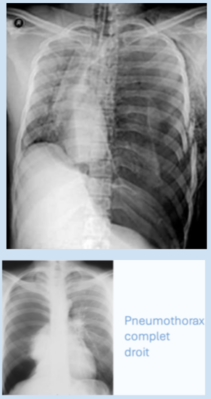

Pour la 2ème image la tâche noire rend surement compte du fait qu'il n'y a que de l'air et plus du tout d'alvéoles dans cette partie en bas à droite alors que pour le reste du poumon droit il y a encore des éléments qui sont présents et qui atténuent les rayons X d'où une densité supérieure.